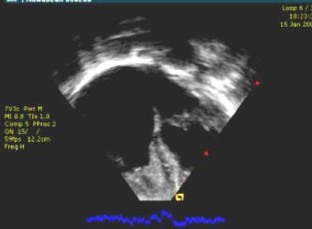

Fig. 1

Movie clip 1 Two-dimensional echocardiogram. The apical four-chamber view shows complete obliteration of the apical portion of the right ventricle. (MOV 2529 kb)

Movie clip 2 Color echocardiogram in an apical four-chamber view showing dense obliteration of the right ventricle apex and severe tricuspid regurgitation. (MOV 2773 kb)